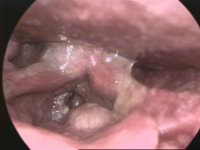

Larynx cancer - endoscopic view | |

سرطان الحنجرة Laryngeal cancer، أو laryngeal carcinoma، هو في الغالب أحد سرطانات الخلية الحرشفية، تعكس أصلها من جـِلد الحنجرة.